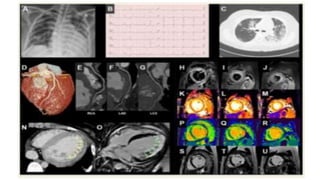

MYOCARDITIS

• Limited clinical experience indicates that SARS-CoV-2 may lead to fulminant myocarditis;

• • Myocarditis should be suspected in patients with COVID-19 and acute-onset chest pain, ST

segment changes, cardiac arrhythmia and haemodynamic instability. In Last updated on 21 April

2020. © The European Society of Cardiology 2020. All rights reserved Page | 58 addition, LV

dilatation, global/multi-segmental LV hypocontractility (on POC echocardiography), and significant

increase in cardiac troponin and BNP/NTproBNP levels, without significant CAD could also be

present;

• • Suspicion of myocarditis should be raised in COVID-19 patients with acute HF/CS without pre

existing CV disorder;

• • CCTA should be the preferred approach to rule out concomitant CAD;

• • CMR (if available) may be used for further diagnostic assessment;

• • Endomyocardial biopsy is not recommended in COVID-19 patients with suspected myocarditis;

• • No clear recommendation can be given for SARS-CoV-2-associated myocarditis treatment.

Potential Heart Injury in COVID‐19

• As with SARS, patients with COVID‐19 also showed potential cardiac injuries. Chen et al reported that among

the 99 confirmed COVID‐19 patients admitted to Wuhan Jinyintan Hospital, 13 (13%) presented elevated

creatine kinase and 75 (76%) showed the elevation of lactate dehydrogenase.3 Wang et al described the

clinical characteristics of 138 hospitalized COVID‐19 patients at Zhongnan Hospital of Wuhan University and

found elevated hypersensitive troponin I in 10 (7.2%), whereas 23 (16.7%) had arrhythmia.4 Besides, Guan

et al extracted the data on 1099 COVID‐19 patients from 552 hospitals in 31 provinces/provincial

municipalities and found that 90 of 675 (13.7%) were with an elevated creatinine kinase level and 277 of 675

(37.2%) showed an increased lactate dehydrogenase level.5 The myocardial dysfunction can be indirect,

caused by reduced oxygen supply, severe lung failure, and the cytokine storm after the SARS‐CoV‐2 infection.

However, there is also the possibility that it might be attributable to the decreased activity of ACE2 in the

heart, just like SARS. Oudit et al18 detected the presence of SARS‐CoV and a marked decreased ACE2

expression in the heart of intranasal SARS‐CoV–infected mice. They also reported that SARS‐CoV was isolated

from 7 of 20 of the human autopsy hearts, and the myocardial damage was accompanied by the decreased

protein expression of myocardial ACE2 as well. Recently, an autopsy case of COVID‐19 was reported in

Chinese.19 Liu et al19 observed a moderate amount of transparent light‐yellow liquid in the pericardial cavity

and mild epicardial edema in an 85‐year‐old man who died from COVID‐19. They also reported that the

myocardial section was gray‐red fish‐like. Considering that this old patient showed a history of coronary

heart disease, whether the myocardial injury was associated with SARS‐CoV‐2 infection is still unclear.

However, direct evidence demonstrating that SARS‐CoV‐2 infects the heart and decreases the ACE2

expression is currently lacking.